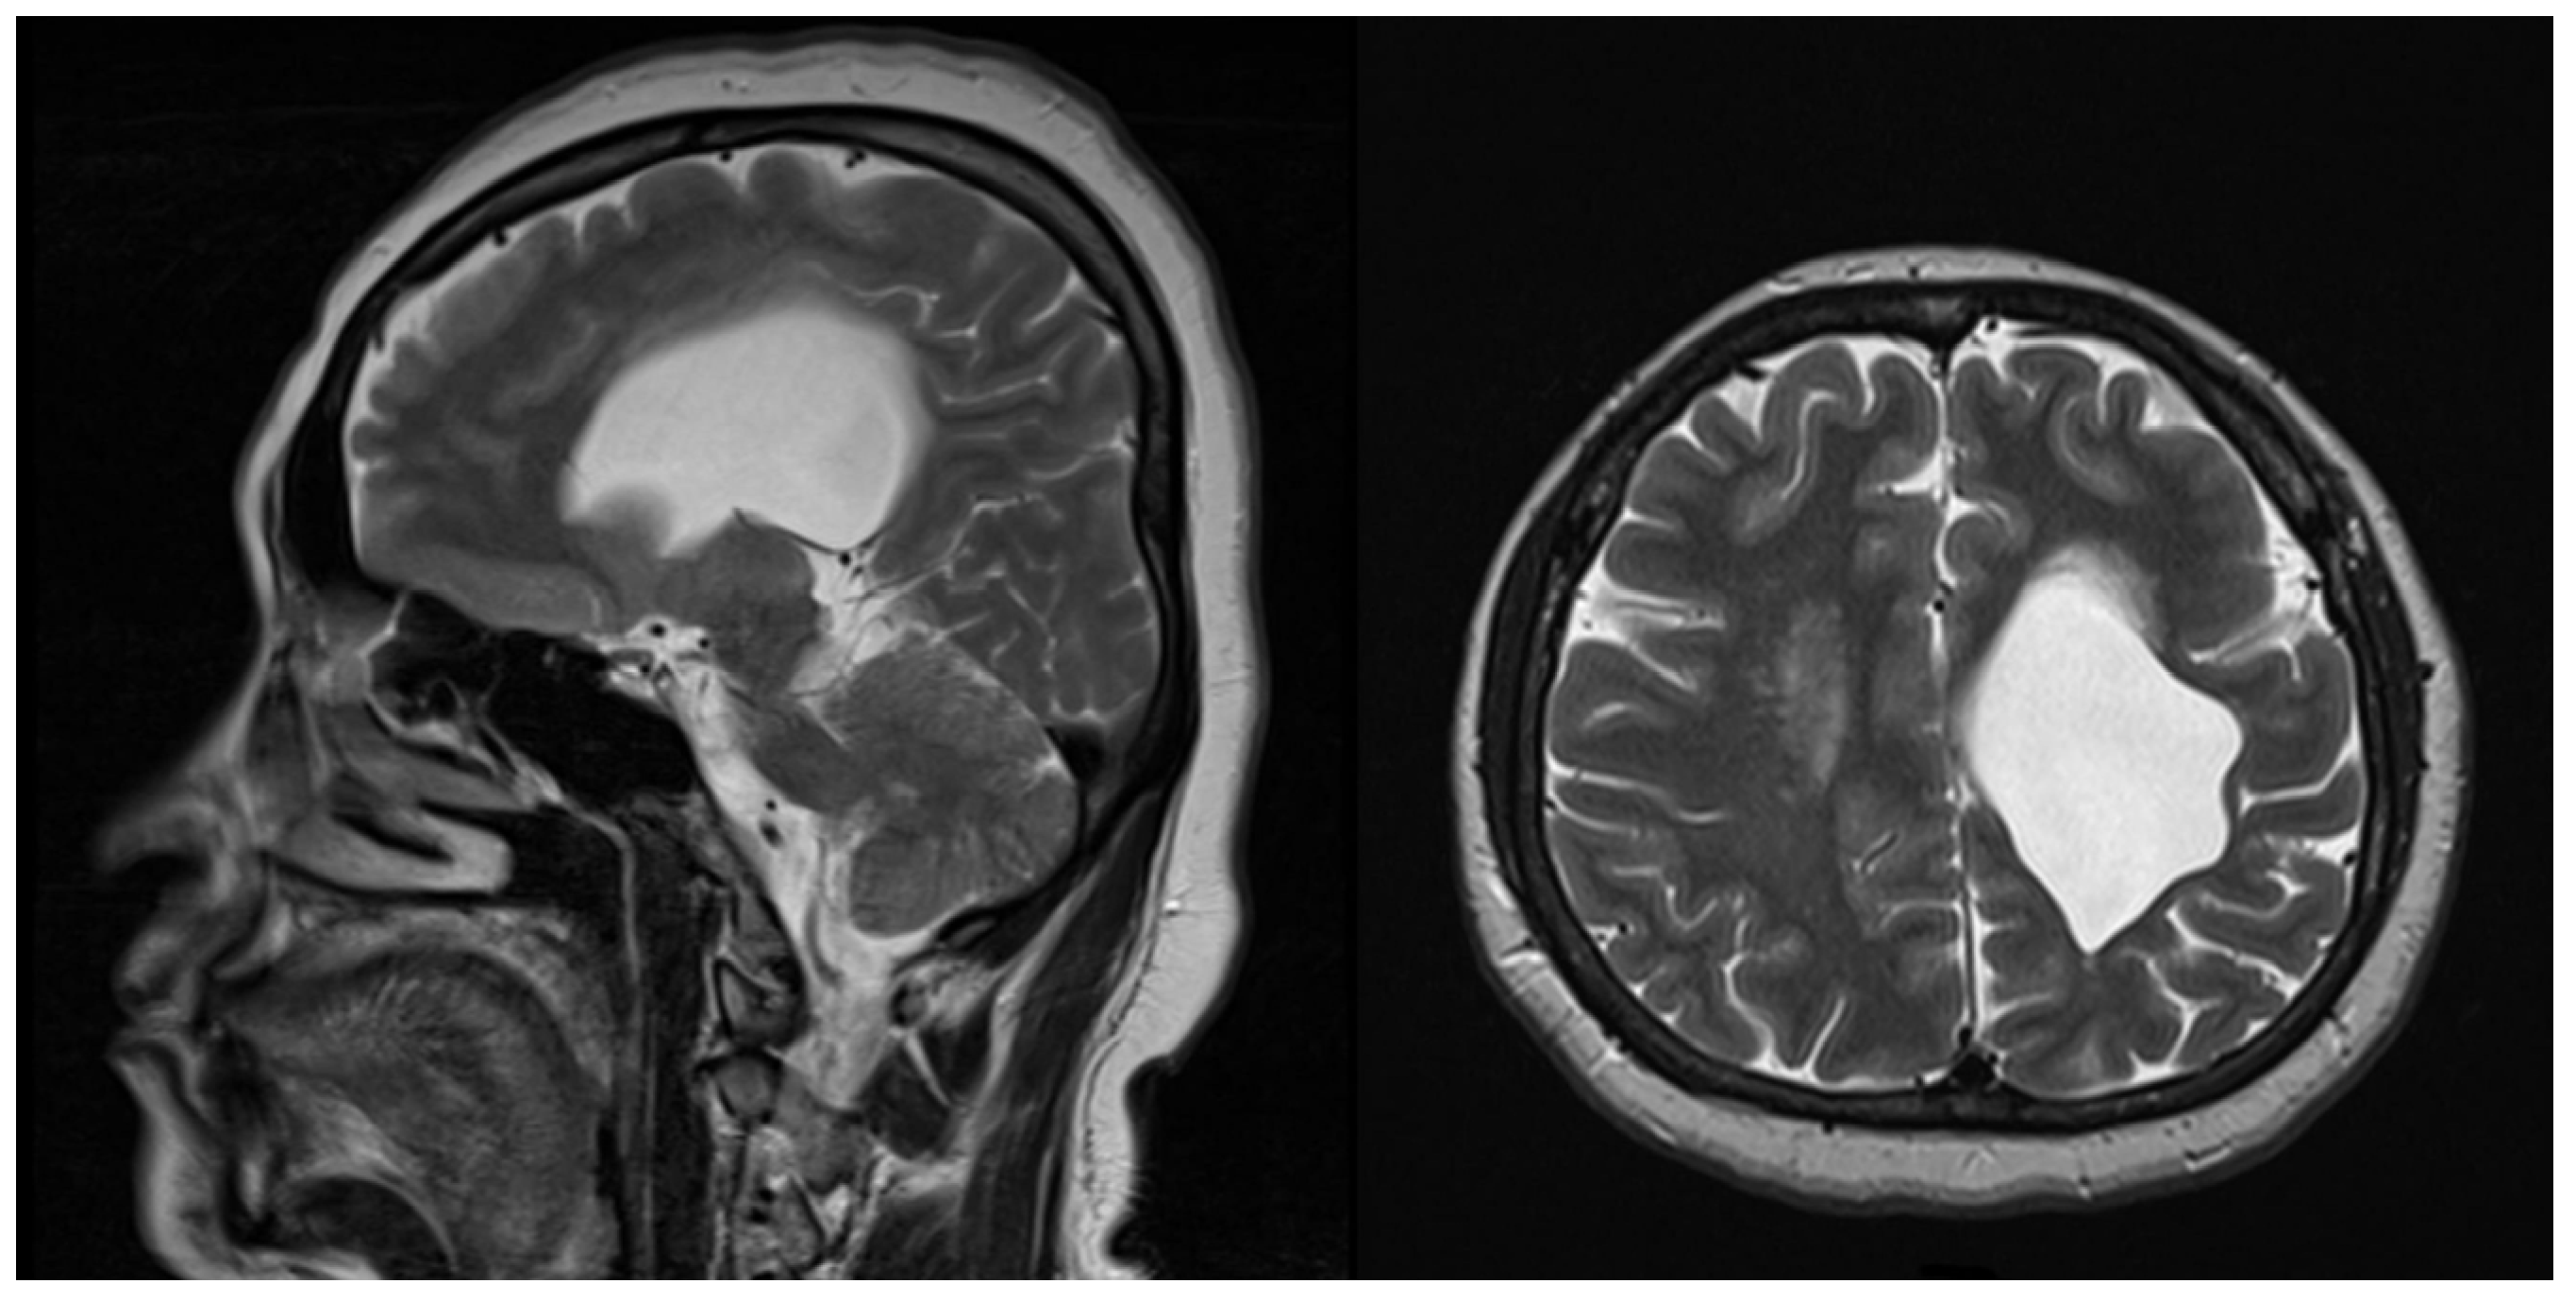

2. Case Description